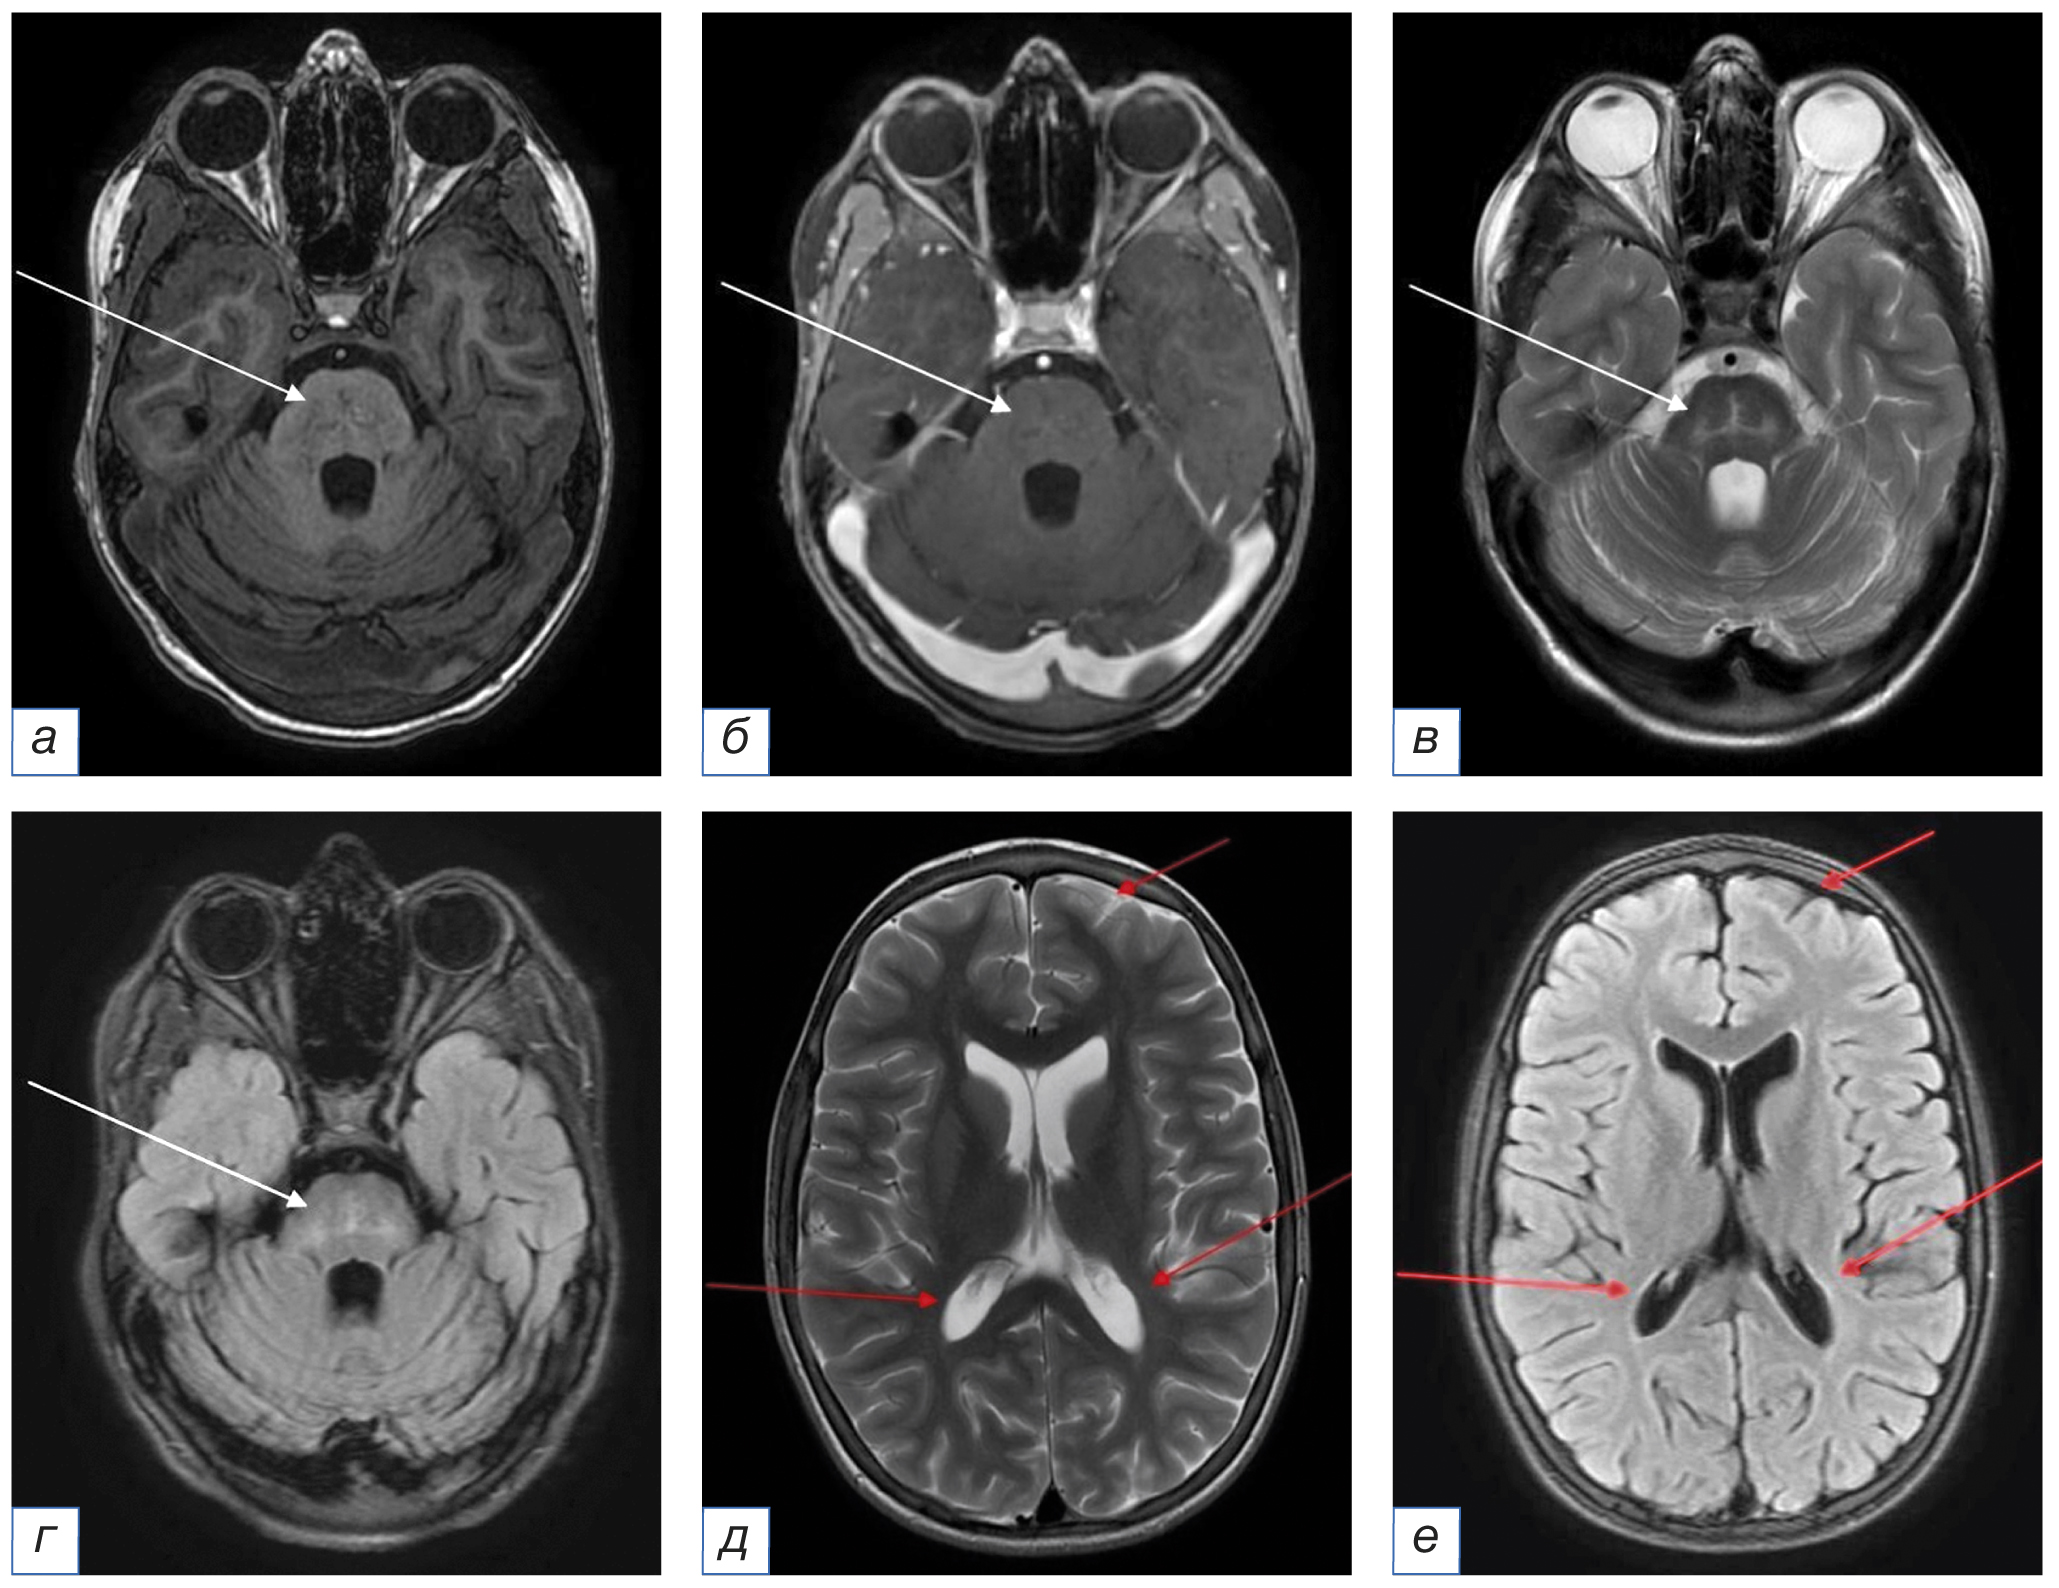

12.03.2020. При первичной МРТ (рис. 1) визуализированы множественные контрастпозитивные очаги, не ограничивающие диффузию, располагающиеся преимущественно субтенториально в мосту и распространяющиеся на мозжечковые ножки и белое вещество мозжечка. Выявляются единичные супратенториальные очаги, расположенные в базальных ганглиях. В качестве лечения проведен кратковременный курс пульс-терапии.

Рис. 1. Первичное МРТ головного мозга в аксиальной плоскости от 12.03.2020 без внутривенного контрастного усиления (a, в — режим Т2-ВИ; б, г — режим FLAIR): определяются множественные билатеральные точечные и криволинейные мелкие очаги измененного МР-сигнала, в том числе сливного характера, расположенные в мосту, мозжечковых ножках и белом веществе гемисфер мозга и мозжечка (стрелки). / Fig. 1. Primary MRI of the brain in the axial plane of March 12, 2020 without intravenous contrast enhancement (a, в — T2-weighted image; б, г — FLAIR): there are multiple bilateral punctate and curvilinear small foci of the altered MR signal, including confluent foci, located in the pons, cerebellar peduncles and the white matter of the brain hemispheres and cerebellum (arrows).